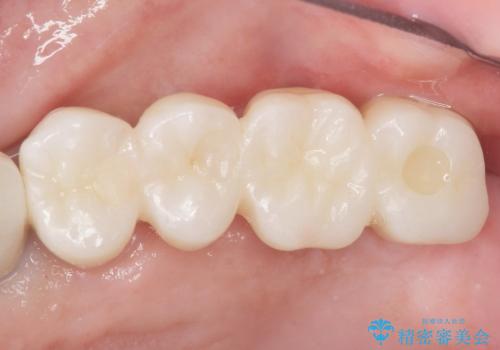

![[ 途中からの治療 ] 他院で行った根管治療後のセラミック治療の症例 治療後](https://seimitsushinbi.jp/wp/wp-content/uploads/2021/08/8f8d20667c9105de80d21401ceb4478d-500x350.jpg?v=1629978239)

![[ 歯牙破折 ] 違和感のある大臼歯 ブリッジ治療の症例 治療後](https://seimitsushinbi.jp/wp/wp-content/uploads/2021/08/2e4ccba27e1ea02fdacf49749694bbb1-500x350.jpg?v=1629711051)